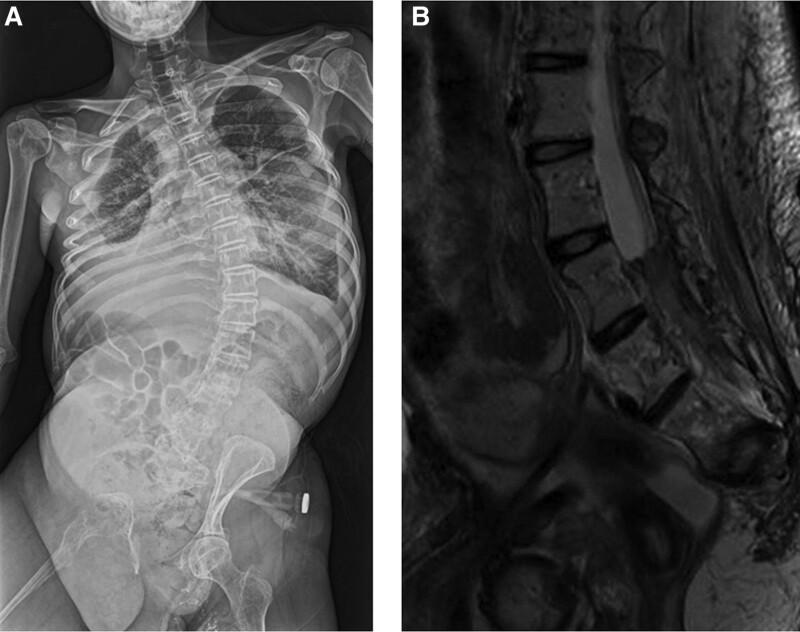

The patient presented with a chylothorax and cerebrospinal fluid leakage. She was treated with sirolimus and an epidural blood patch, and her symptoms resolved. Computed tomography and magnetic resonance imaging revealed an epidural hematoma extending from L3 to the caudal region, and blood results revealed a consumption coagulopathy.

患者出现乳糜胸和脑脊液漏。她接受了西罗莫司和硬膜外血贴治疗,症状缓解。计算机断层扫描和磁共振成像显示硬膜外血肿从 L3 延伸至尾骨区域,血液检查结果显示消耗性凝血病。